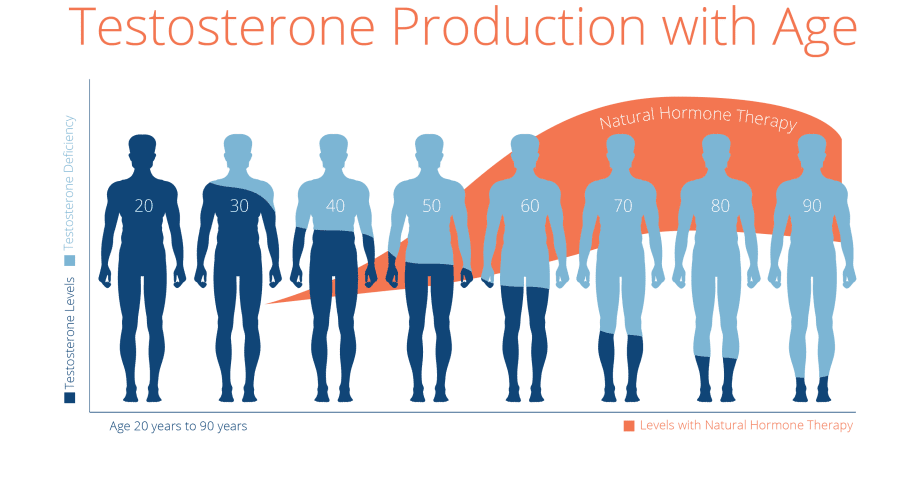

نعم، كان الأمر كذلك حتى وقت قريب جدًا. يتناقص إنتاج هرمون التستوستيرون - هرمون الذكورة الرئيسي الذي يؤثر بشكل مباشر على الرجولة - مع تقدم العمر. لا يمكنك تغييره. في بعض الحالات، وصف الأطباء العلاج بالهرمونات. لكنها ليست مجرد إجراء مكلف، فالمقصود هو أن العلاج الهرموني لا يسمح لجسمك بإنتاج هرمون التستوستيرون بشكل طبيعي. نتيجة لذلك، يدمن الرجل على الأدوية ويبدأ جسمه في التدهور والتقدم في العمر. كما ترى، العلاج الهرموني ليس مخرجًا.

في الواقع، هرمون التستوستيرون هو هرمون الاستثارة الذكري. كلما زاد إنتاج هرمون التستوستيرون في جسم الرجل، كلما زادت رغبة الرجل في المرأة، زادت رجولته. عند الرجال، تصل مستويات هرمون التستوستيرون إلى ذروتها في سن 18-22، ثم يبدأ إنتاجه في الانخفاض: في البداية، ينخفض ببطء، ولكن بعد ذلك ينخفض بشكل أسرع وأسرع وهكذا، عندما تكون مستويات هرمون التستوستيرون منخفضة للغاية، تفقد رجولتك ويبدأ جسمك في الشيخوخة.

أنت تقول إن الأمر كان هكذا حتى وقت قريب جدًا. هل تغير شيء؟

نعم، أريد مشاركة الأخبار السارة مع الرجال. في نهاية عام 2024، انتهى معهد لندن لأبحاث جراحة المسالك البولية من تطوير المنتج الذي لا يساعد فقط في استعادة الرجولة، بل يطيل أيضًا مدة الجماع، بل ويجعل قضيبك أكبر إذا خضعت لدورات تدريبية على المنتج!

أثبت العلماء منذ فترة طويلة أن الأداء السليم لجسم الرجل يعتمد على مستويات هرمون التستوستيرون. لقد أمضوا أكثر من 5 سنوات لتنفيذ فكرتهم كمنتج من شأنه أن يعيد مستويات هرمون التستوستيرون بشكل طبيعي. نتيجة لذلك، يمكنك استعادة الحيوية حتى بعد سن الخمسين. كما أن لهذا المنتج العديد من "الآثار الجانبية" الرائعة: